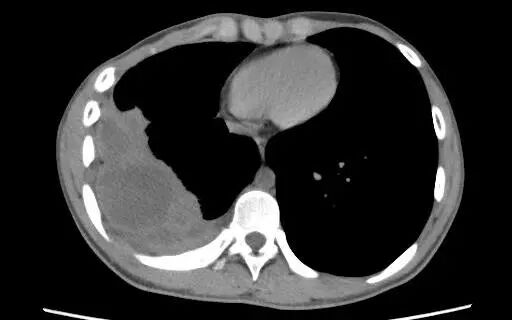

出院后,白某某坚持每月复查,规律用药。近日,在他术后整整一年的复查中,胸部CT清晰显示:原先的病变区域已显著吸收好转,右侧胸腔结构基本恢复正常,肺功能得到有效保护。